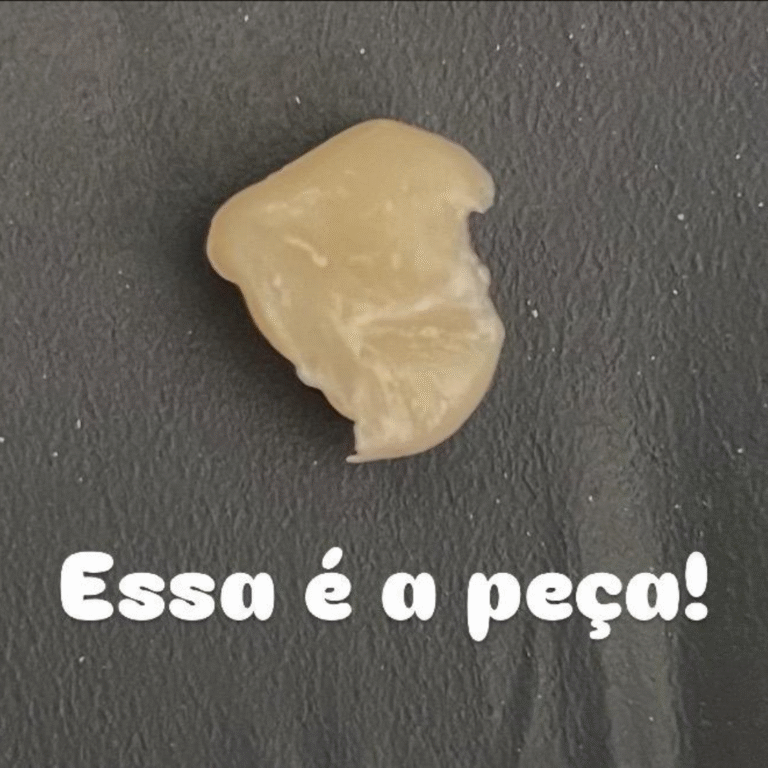

🔸 Como realizar a técnica completa de resina indireta em dentes posteriores, do preparo à cimentação final.

Como confeccionar e adaptar resinas indiretas com precisão e naturalidade.